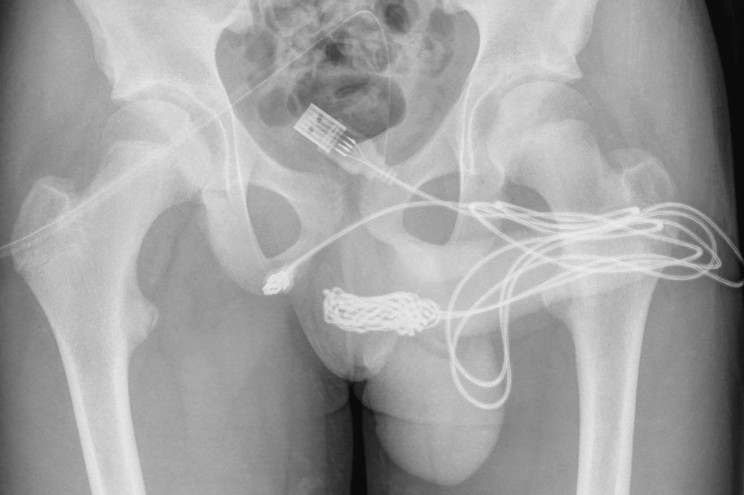

Initial attempts to remove it failed. After getting it X-rayed the surgeons decided the best way to get it out was to open up his gooch, between his penis and butthole to yank it out. Literally pulling the plug on the boy's nasty ordeal.